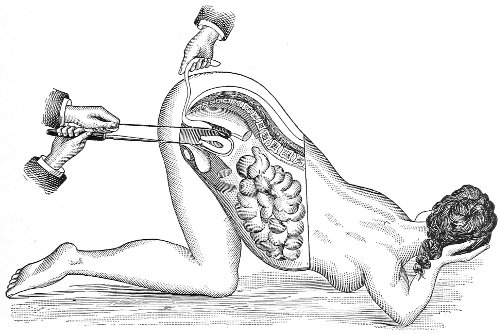

Examination of External Genitals and Pelvic Structures.—To examine the external organs of generation and the pelvic viscera the woman should be placed upon a table. In some cases the physician may be obliged, for want of proper facilities or on account of the physical condition of the patient, to make his examination upon a bed. Such an examination, however, is never so satisfactory or so thorough as the examination made with the woman upon the examining-table. A great number of gynecological tables have been introduced. The one which seems to the writer the best, on account of its simplicity and the perfect relaxation of the abdominal muscles furnished by it, is shown in the accompanying illustration (Fig. 1). It is a plain wooden table, at the foot of which are attached the upright supports for holding the stirrups for the feet, such as have been devised by Dr. Edebohls. By this arrangement the feet and legs are supported without any effort on the part of the woman; when the buttocks are drawn well down to the foot of the table there is a certain amount of flexion 23 of the pelvis upon the trunk, and the most complete attainable relaxation of the abdominal muscles is secured.

Fig. 1.—Woman in the dorsal position with feet supported in Edebohls’ stirrups.

Vaginal and Bimanual Examination.—Having examined and noted the condition of the external genitals, the physician should next proceed to examine the vagina. The index finger of the right or the left hand should be gently introduced into the vagina. The condition of the vaginal walls, and the direction, consistency, form, etc. of the vaginal cervix, may be determined. The shape and size of the os uteri should be noted. The ulnar edge and the tips of the fingers of the other hand should then be placed upon the abdomen, immediately above the symphysis pubis, and gently pressed backward and downward toward the vaginal finger 24 (Fig. 2). In this way the various pelvic organs, the uterus, Fallopian tubes, ovaries, and ureters, may be palpated between the two hands, and their position, size, shape, and consistency may be determined. Such an examination is, of course, made much more easily in a thin woman than in a fat one. A thin woman a few weeks after labor may be examined most easily, on account of the relaxation of the abdominal and vaginal walls.

Fig. 2.—Bimanual examination.